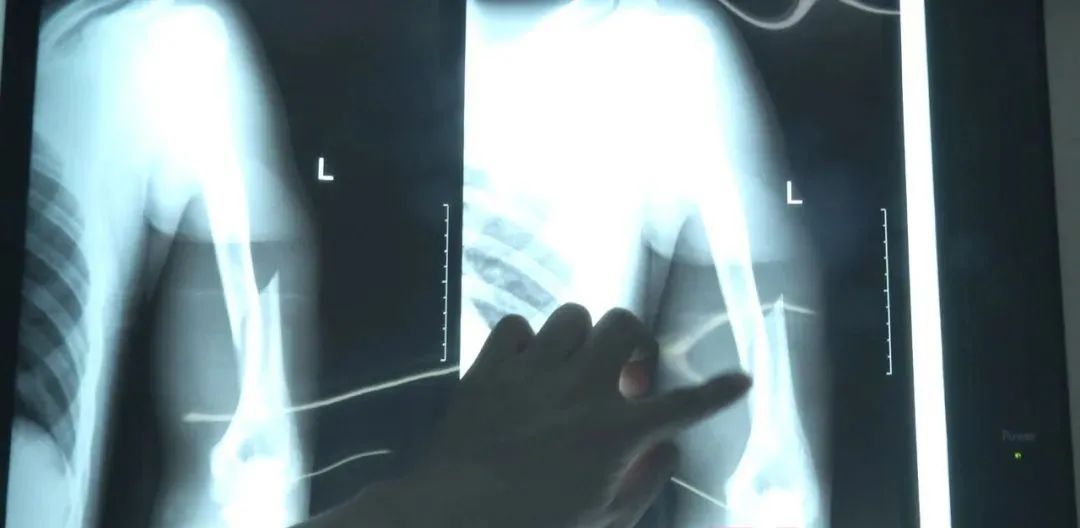

忍着剧痛的小刘被紧急送往医院,做完相关检查后,他被确诊为左肱骨中下段粉碎性骨折,由于骨折较为严重,需要立即进行相关处理。

医生表示,因为移位很明显痛感剧烈,因此要先帮小刘止痛,再进行手术。做术前准备的时候,医生对他进行了骨密度检测,结果显示,小刘的骨密度检测结果竟然低至-3.5,比很多老年人的骨密度还差,这也是掰个手腕就能把他的手臂给掰断了的直接原因。